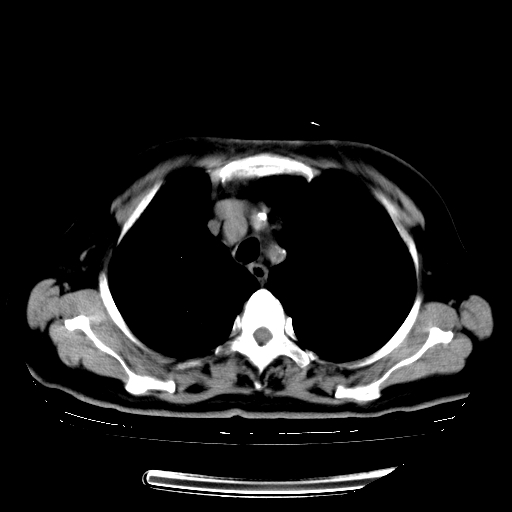

女,70岁,咳嗽、咳痰一个月,低热一周。

1.左上肺结核,部分纤维化。右肺中下叶部分肺不张,内见液化、坏死及点状钙化,右中下叶支气管壁增厚、管腔狭窄,见多个点状钙化,结合临床考虑支气管内膜结核,建议痰检查抗酸杆菌并参考血沉。两肺多个小圆点状高密度灶,境界模糊,多考虑结核肺内播散。但本人年龄较大首先应支气管镜检以除外右肺癌。

2.胸主动脉夹层。